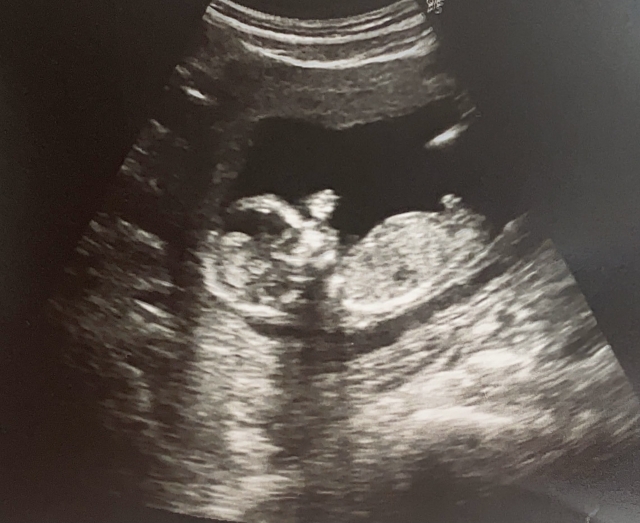

妻子原本已結紮,為了生回孩子,決定再做接通手術,而她原本可進行更簡單,且受孕率相同的試管嬰兒療程,卻不願意並直言「我把門再度打開,如果是他,他自己會找得到路回來。如果是做試管,我怎麼會知道是不是他回來了呢?」

值得一提的是,妻子秉持著這份信念,果然不久有喜,當她懷孕8個多月時,前一胎的兒子突托夢表示「我很快就要回去找你們了。」原本她認為只是日有所思、夜有所夢,結果不到一週孩子就出生了,生日為6月10日。

施景中指出,6月10日剛好和妻子、先生同一天生日,「小孩依約回來了」。施景中回憶,他第一次遇見夫妻倆時,小孩尚未出生,聽到2人的遭遇,深深嘆息。他也曾在臉書寫下「就算冬天再寒冷,春天仍會依約到來」,以此替夫妻倆祝福,如今孩子出生,「春天真的回來了」。